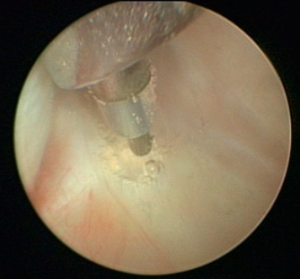

顎関節鏡検査のもう一つの適応症は、再発性顎関節脱臼の治療です。繰り返し脱臼する関節の椎間板後部付着部を硬化させることにより、最小限の侵襲で将来の脱臼を回避します(図1)(4、5)。